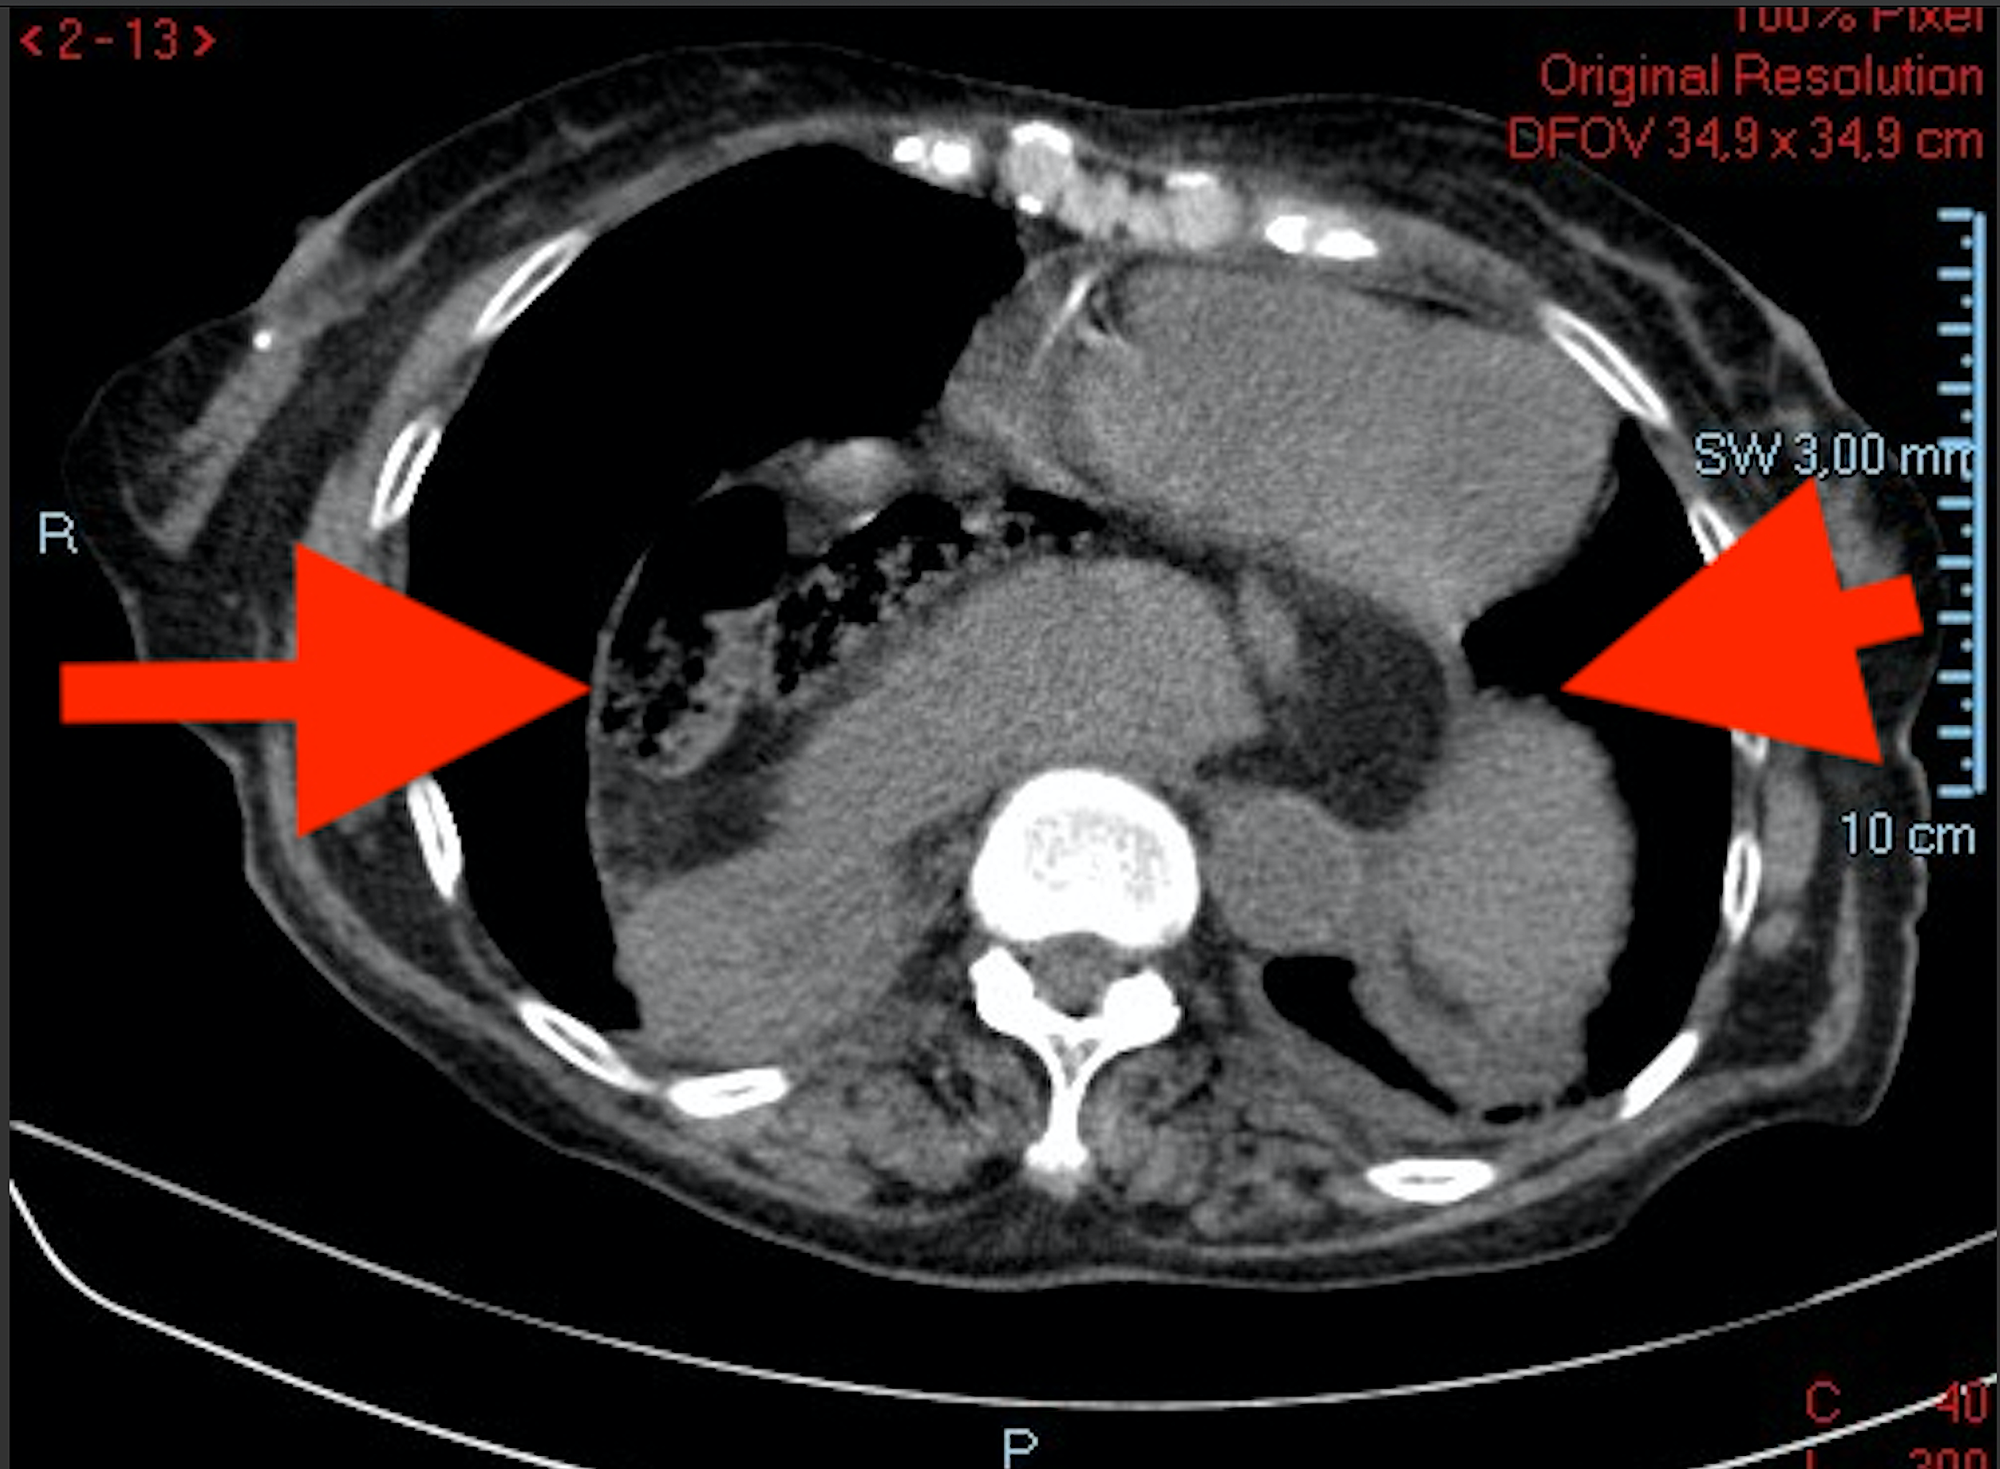

Gastric volvulus with perforation Image Radiology Gastric Volvulus the radiologists were 90% accurate (55/61 with six misclassifications of gastric volvulus as a hiatal hernia for each reader). — gastric volvulus is characterized by rotation of the stomach along its long or short axis leading to. — the stomach is suspended at the esophageal hiatus by four ligaments, namely the gastrohepatic, gastrocolic, gastrosplenic and. —. Radiology Gastric Volvulus.

Radiological features of acute gastric volvulus in adult patients Clinical Imaging Radiology Gastric Volvulus the radiologists were 90% accurate (55/61 with six misclassifications of gastric volvulus as a hiatal hernia for each reader). — gastric volvulus is characterized by rotation of the stomach along its long or short axis leading to. — the various imaging appearances of volvulus of the gastrointestinal tract are described, with. — ménétrier disease is a. Radiology Gastric Volvulus.

CT of Gastric Volvulus Interobserver Reliability, Radiologists' Accuracy, and Imaging Findings Radiology Gastric Volvulus — gastric volvulus is characterized by rotation of the stomach along its long or short axis leading to. — ménétrier disease is a rare overgrowth of gastric mucus cells and can appear with imaging features similar to. — the various imaging appearances of volvulus of the gastrointestinal tract are described, with. — the stomach is suspended. Radiology Gastric Volvulus.